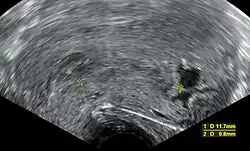

Ultrasound criteria

A review article in The New England Journal of Medicine based on a consensus meeting of the Society of Radiologists in Ultrasound in America (SRU) has suggested that miscarriage should be diagnosed only if any of the following criteria are met upon ultrasonography visualisation:[110]

| Crown-rump length of at least 7 mm and no heartbeat. | Crown–rump length of less than 7 mm and no heartbeat. | [110][111] |

| Mean gestational sac diameter of at least 25 mm and no embryo. | Mean gestational sac diameter of 16–24 mm and no embryo. | [110][111] |

| Absence of embryo with heartbeat at least 2 weeks after an ultrasound scan that showed a gestational sac without a yolk sac. | Absence of embryo with heartbeat 7–13 days after an ultrasound scan that showed a gestational sac without a yolk sac. | [110][111] |

| Absence of embryo with heartbeat at least 11 days after an ultrasound scan that showed a gestational sac with a yolk sac. | Absence of embryo with heartbeat 7–10 days after a scan that showed a gestational sac with a yolk sac. | [110][111] |

| Absence of embryo at least 6 weeks after last menstrual period. | [110][111] | |

| Amniotic sac seen adjacent to yolk sac, and with no visible embryo. | [110][111] | |

| Yolk sac of more than 7 mm. | [110][111] | |

| Small gestational sac compared to embryo size (less than 5 mm difference between mean sac diameter and crown-rump length). | [110][111] |